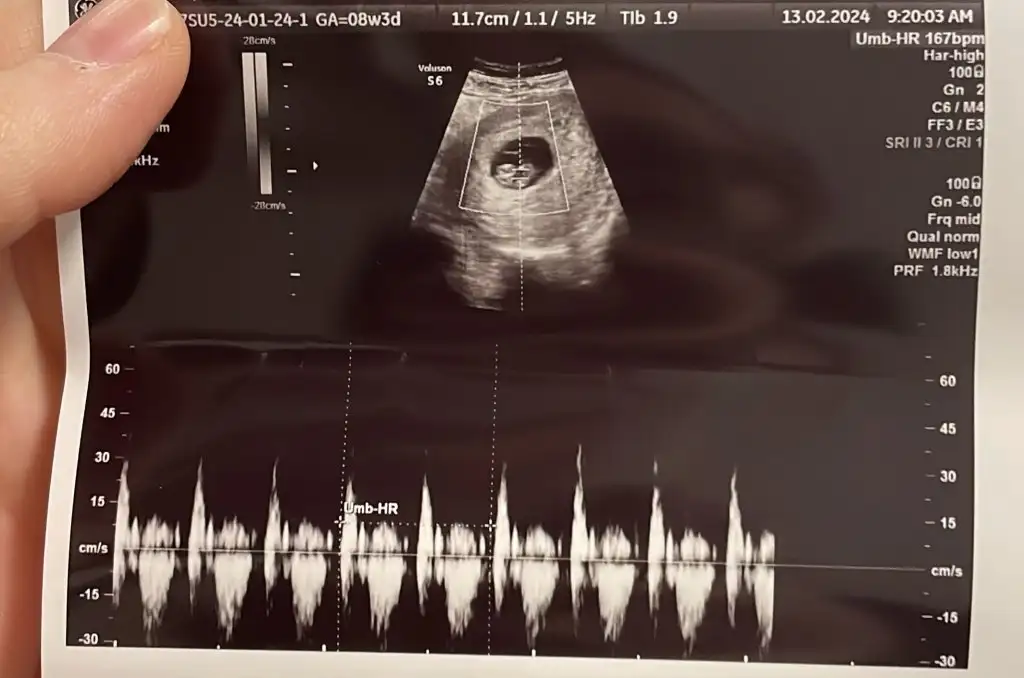

Benim bebitoOrtadaysa ne olur

Canım banada bakar mısınBenim bebito

ortafa görünüyor ama dikkatli bakınca solda plesenta görünüyor

Plasenta nerde anlamıyorum benCanım banada bakar mısın